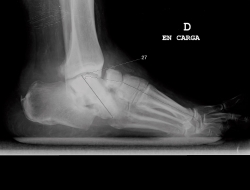

Cada vez más publicaciones evidencian que, en pacientes seleccionados, un tratamiento quirúrgico temprano ofrece una corrección y estabilización de la deformidad(8). Algunos estudios plantean que los ángulos radiológicos pueden ser predictores de complicaciones; Wukich et al.(9)definen un límite de 27 grados de alteración de la línea de Meary en la proyección de perfil como predictor de la aparición de úlceras (Figura 1).